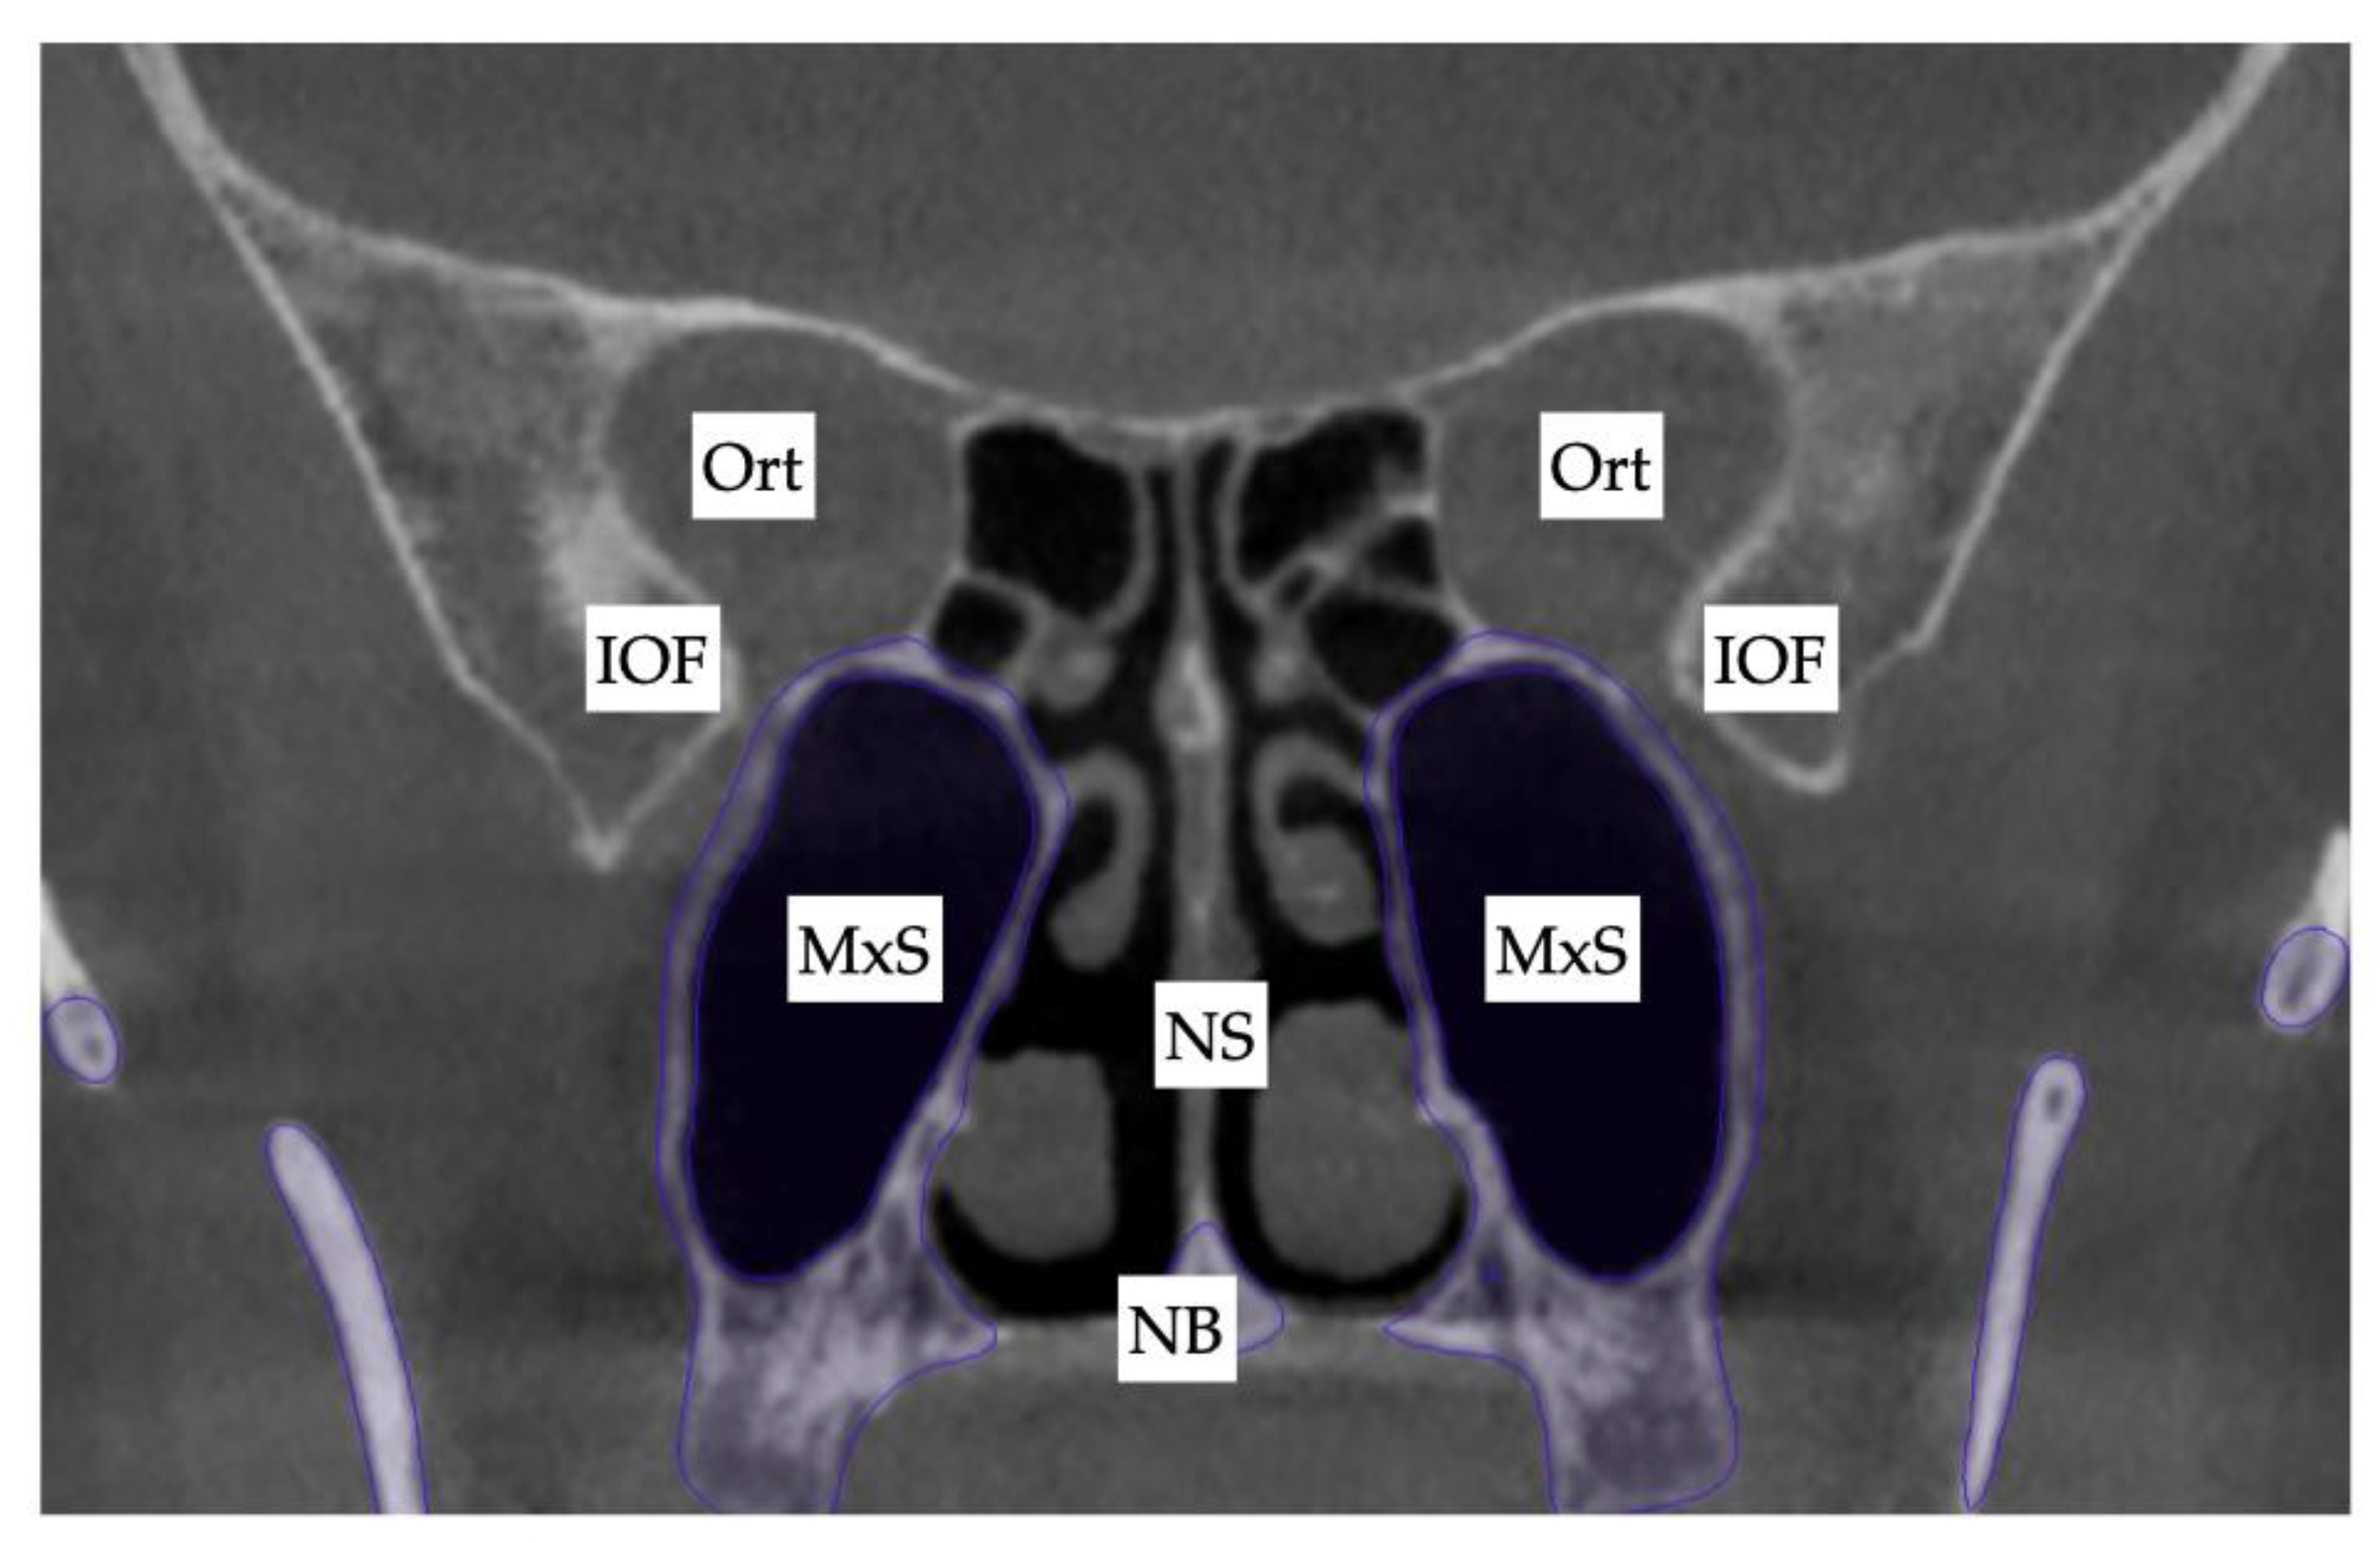

Due to the tooth-bone-borne nature of the appliance, its placement is limited by the shape of the hard palate and its outline, the yaw of the palatal (maxillary base) plane, and its relationship to the plane connecting the posterior–superior edges of the pterygomaxillary fissure (Figure 10).

Figure 10. The initial inclination (yaw) of the maxillary base at the level of the posterior wall of the maxillary sinuses and the inferior orbital fissure. Ort—Orbit; IOF—Inferior Orbital Fissure; MxS—Maxillary Sinus; NS—Nasal Septum; NB—Nasal Base.